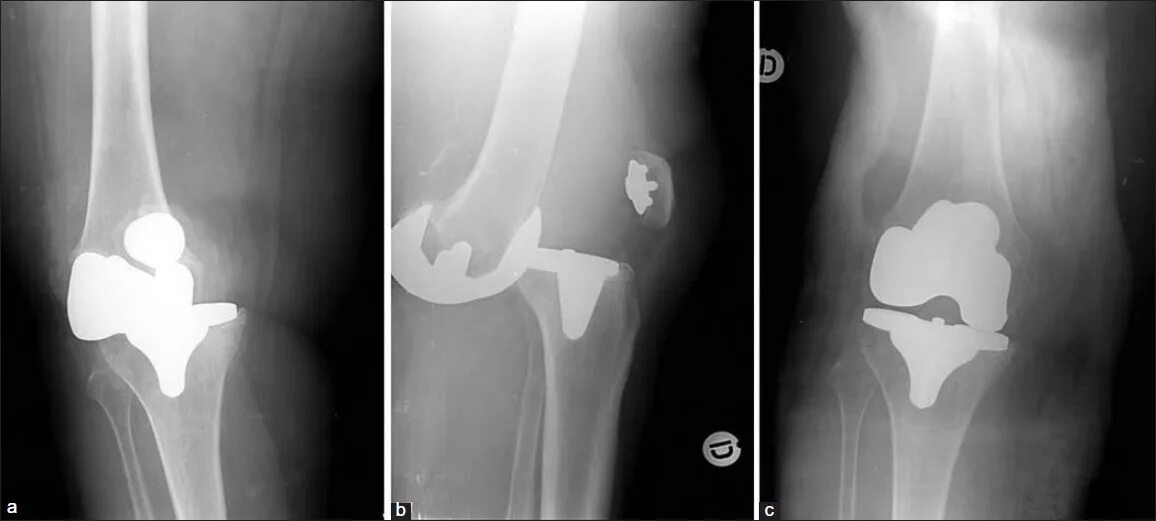

Вывихи после операции тазобедренного сустава